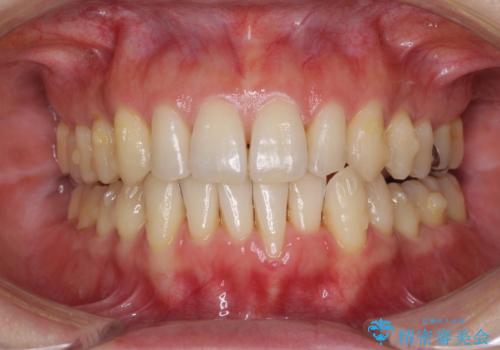

八重歯のインビザライン矯正治療

- 下顎の八重歯と、上下のクロスバイトを気にして来院された患者様です。

インビザラインを用い、下顎全体の後方移動、IPR(歯と歯の間を削る)と歯列全体を拡大させることで、歯並びを整えていくこととしました。

奥に位置していた上の前歯が下の前歯を乗り越える際、奥歯でものを咬むことができず、辛い時期が続きました。